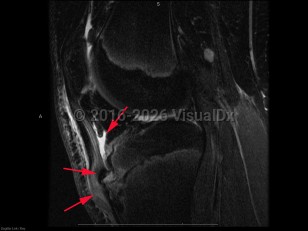

Imaging Studies image of Osgood-Schlatter disease - imageId=8337407. Click to open in gallery.  caption: '<span>Sag intermediate weighted fat  saturated MRI sequence demonstrates bone marrow edema in the region of  the fragmented tibial tubercle, with adjacent patellar tendonosis, and  deep infrapatellar bursitis. These findings are compatible with Osgood  Schlatter disease.</span>'

Sag intermediate weighted fat saturated MRI sequence demonstrates bone marrow edema in the region of the fragmented tibial tubercle, with adjacent patellar tendonosis, and deep infrapatellar bursitis. These findings are compatible with Osgood Schlatter disease.